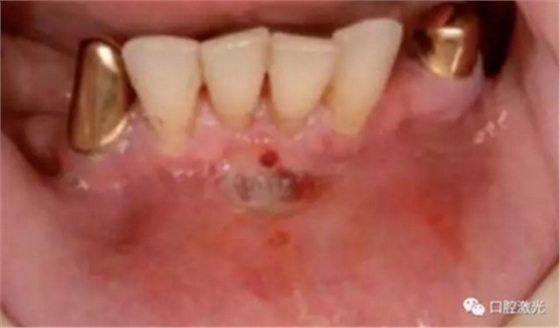

激光对#33病变组织气化切除前(左图)后(右图)

气化切除种植体周围的软组织可以获得一个干净的种植体表面以及去除感染的生物组织层。其目的是稳定种植体周围的组织结构,从而避免骨的缺失导致种植体的失败。但由于种植体的数量逐步增加以及患者年龄的逐渐增大,出现种植体周围炎的概率会显著提高。口腔激光疗法的出现,扩大了种植体周围炎的治疗范围并提供了维持健康的种植体的一种全新方法。